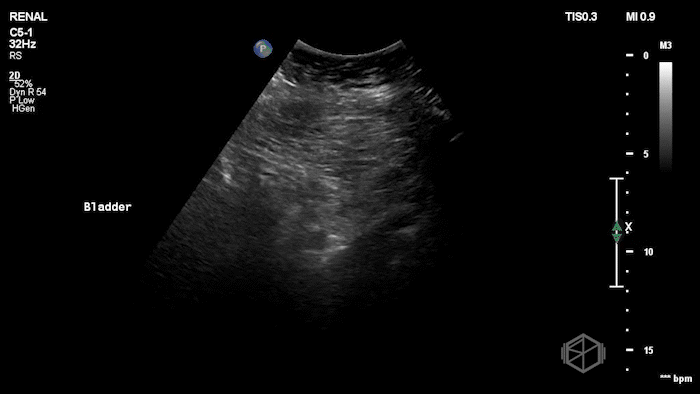

A 70's male with a history of nephrolithiasis presented to the ED with right flank pain worse over the last 4 days. Dr. Mendelow performed a POCUS immediately that showed:

Subsequent CT scanning later showed a 10 x 7 x 7mm right ureterovesical junction calculus within the urinary bladder causing moderate right hydroureteronephrosis, delayed nephrogram and mild perinephric fat stranding. The patient was taken to the OR for scope of bladder and right ureter; laser lithotripsy and removal of right ureteral stone and placement of right ureteral stent.

Diagnosis: 10mm UVJ stone with moderate hydronephrosis